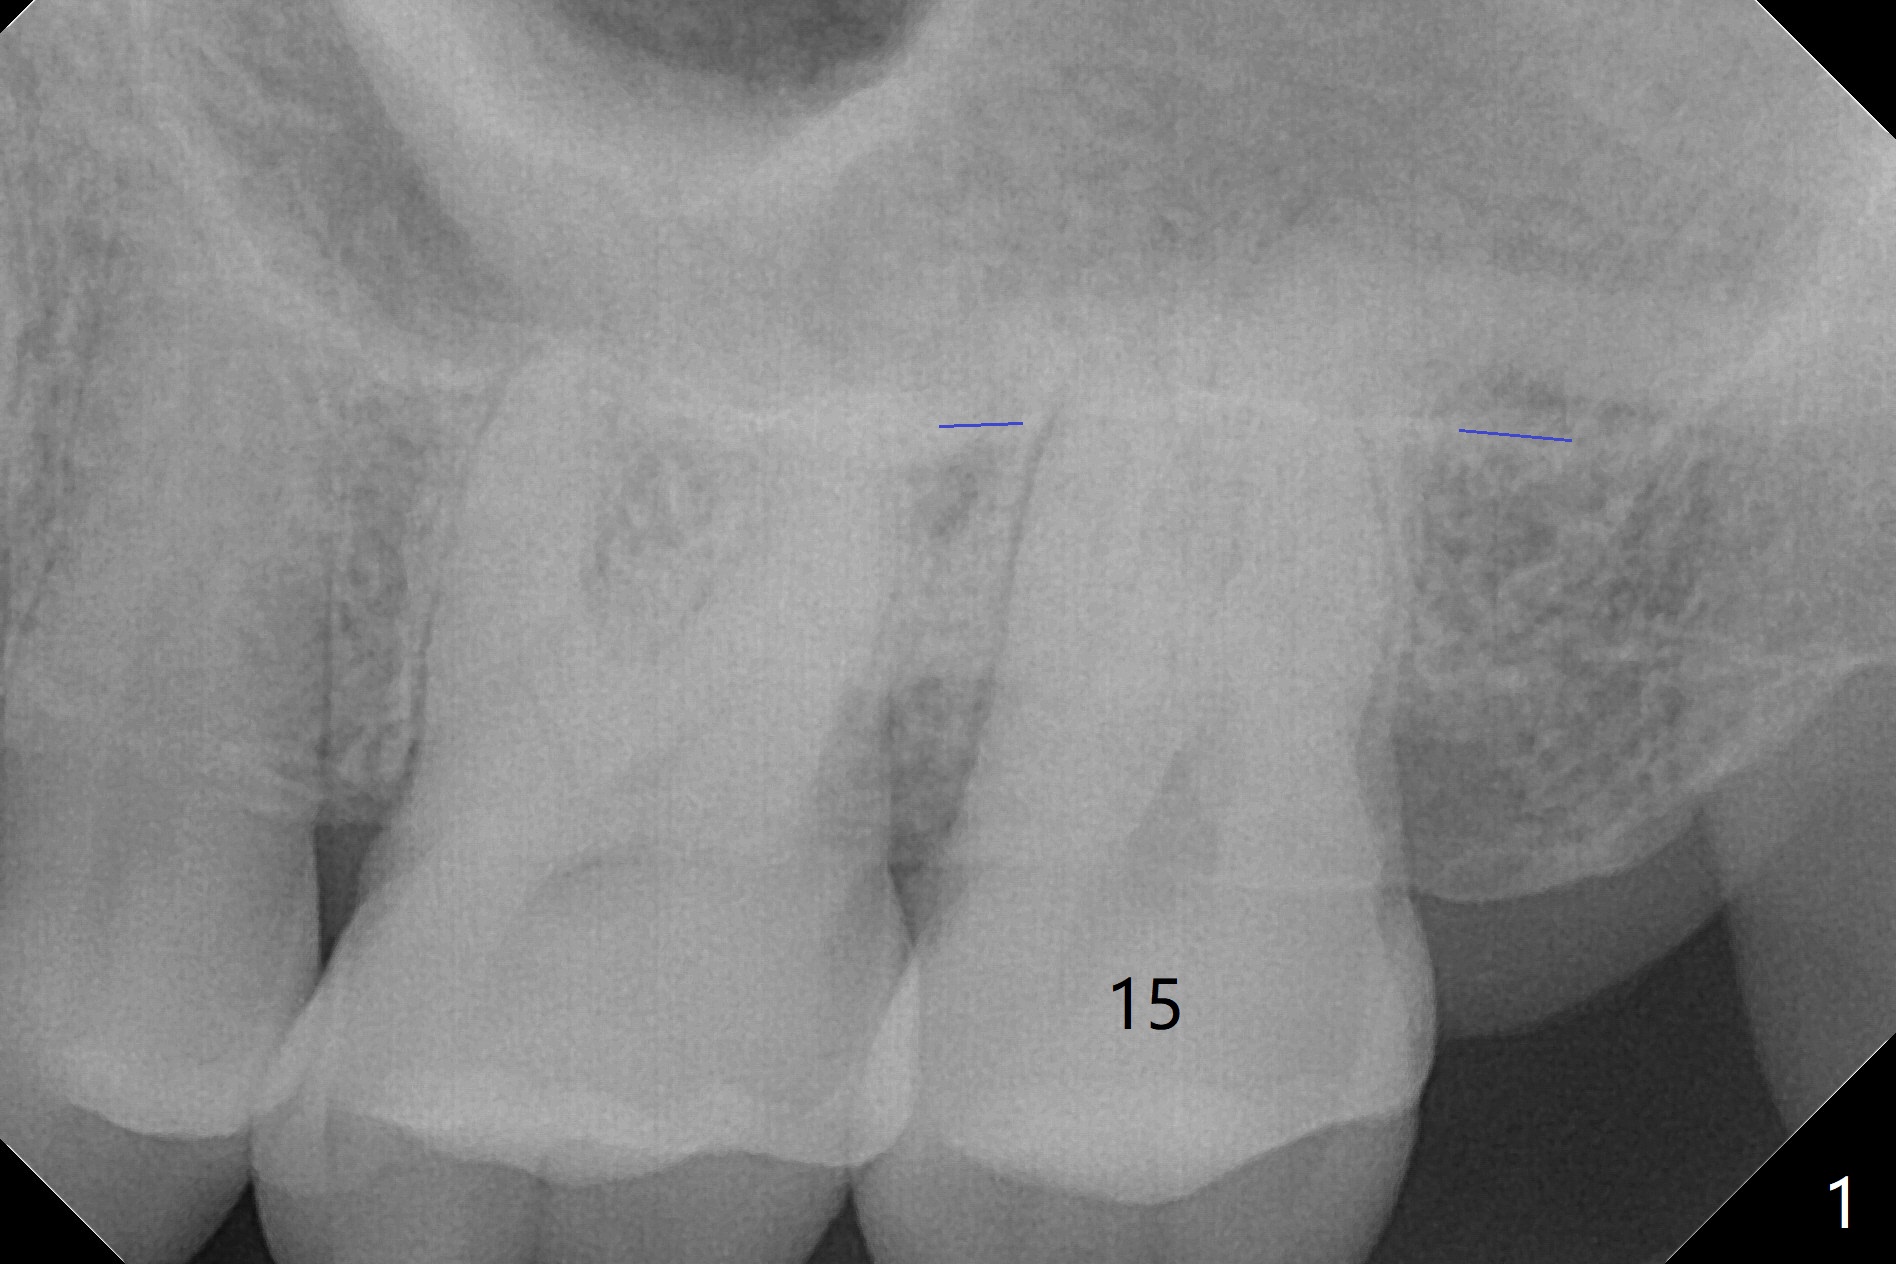

A 49-year-old man has had symptom and sign of crack syndrome at the tooth #15 for 2 years (Fig.1 (blue line: sinus floor)). It finally cracks. There appear to be 3 roots with a thin and relatively short septum after extraction (Fig.2 grey area). Use Pointed/Lindamann bur with 4 mm stop (red line) to start osteotomy, followed possibly with Magic Expander 3 mm if the bone is not so dense. Insert PRF membrane (assistants draw blood) and allograft for sinus lift prior to placement of dummy implants. The definitive one is expected to be 5x10 mm.